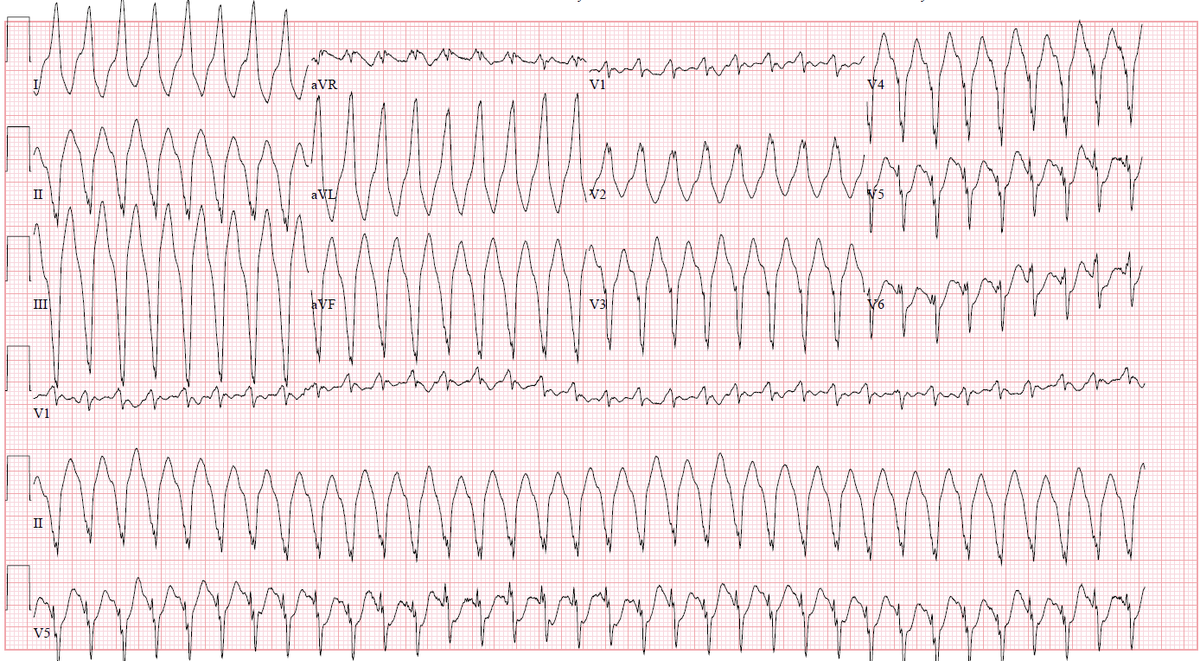

Persistent junctional reciprocating tachycardia (#PJRT) in a 58-yo 👨🏻 with incessant SVT and tachycardia-induced cardiomyopathy

A) ECG during tachycardia: long RP interval with negative P waves in II, III and aVF.